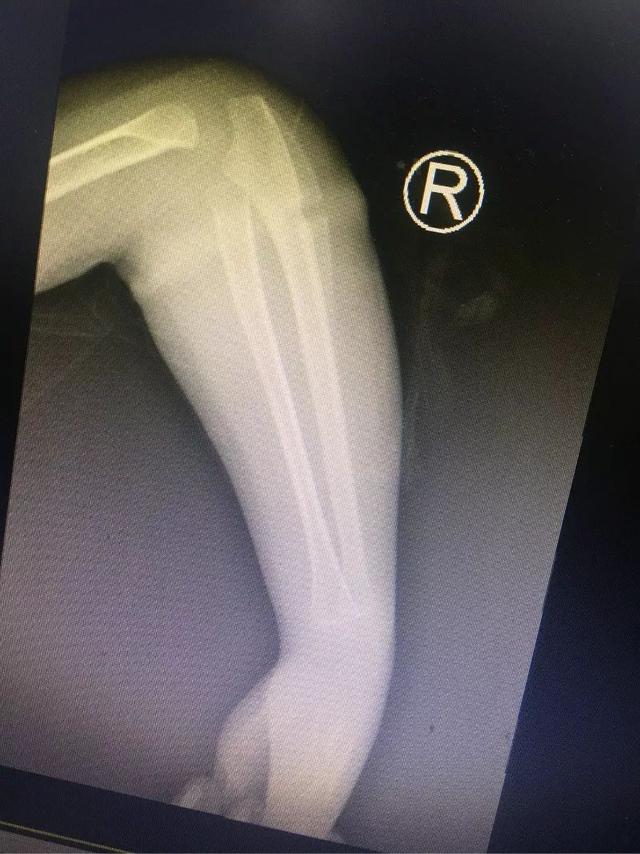

乐乐手臂的X光片。本文图片 都市快报